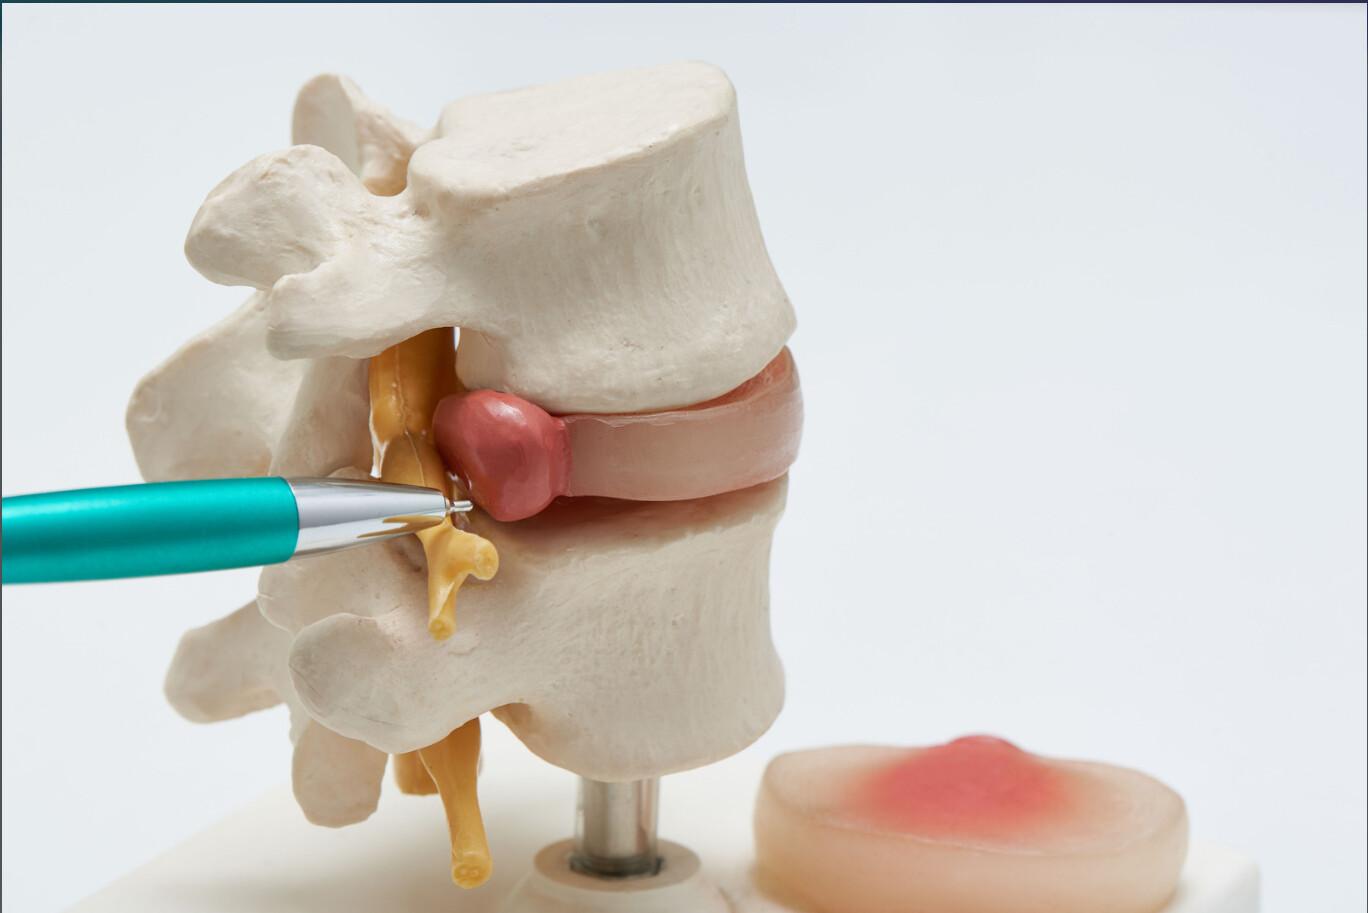

Az alábbiakban megvizsgáljuk a gerinccsatorna szűkületet, tüneteit, a szükséges vizsgálatokat és a lehetséges...

A gerincsérv vizsgálat kiemelten fontos, hiszen a probléma a korai fázisban még visszafordítható. Ebben...

A cikkben a gerincsérv kezelése lesz a górcső alatt. Megtudja, milyen módszerekkel lehet eredményesen...